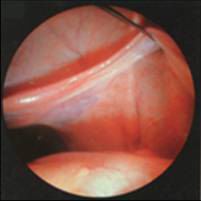

4.腹腔鏡檢查。

至於腹腔鏡在ORS診斷和治療中的套用Howard曾報導關於根據CPP患者病史、非侵襲性試驗的物理診斷和發現的評估,4%以上用腹腔鏡診斷其中約65%的CPP患者至少經腹腔鏡可作出一種診斷:1/3為子宮內膜異位症;1/4為粘連;余為卵巢囊腫、疝、盆腔淤血綜合徵卵巢殘餘物綜合徵等不過腹腔鏡在卵巢殘餘物綜合徵或殘餘卵巢綜合徵中的套用,文獻報導意見尚不一致,有的作者認為其作用有限,有的作者則認為腹腔鏡較其他手術方式價廉、併發症少、住院時間短;Kamprath等認為腹腔鏡尚可經腹膜後進入,在盆腔邊緣分離輸尿管骨盆漏斗韌帶,可有效地切除殘餘卵巢組織。腹腔鏡或剖腹探查的選擇應根據手術困難的程度和手術者的經驗而個體化。